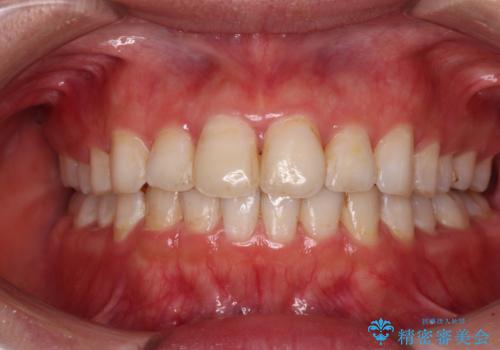

- 八重歯やデコボコをインビザラインで治療したいとのことで来院された患者様です。

インビザライン単体で治療を行うには叢生が強いと判断されたため、事前にワイヤー装置で抜歯矯正を行い、ある程度改善してからインビザラインにて仕上げていくこととしました。